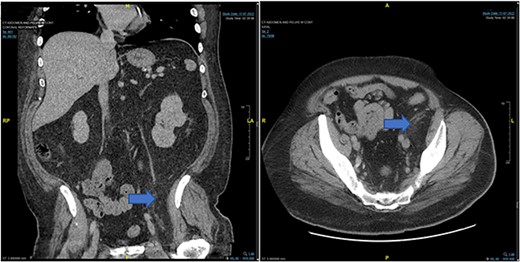

Case 1: CT (axial and coronal view), blue arrow marks hibernoma.

In the emergency department, vital signs were remarkable for elevated blood pressure of 166/81, but otherwise stable and afebrile. WBC count was elevated at 15.4 with left shift and hemoglobin was low at 9.6. Complete Metabolic Panel was notable for hyponatremia of 128, and mildly elevated BUN/serum creatinine of 26/1.5 which was slightly higher than his baseline of 17/1.3. Liver function tests were unremarkable. UA showed likely UTI with positive esterase, high RBC/WBC and bacteria and protein. A CT of the abdomen and pelvis was done, showing a left non-obstructing kidney stone and a left retroperitoneal fat density with stranding along the left iliopsoas measuring 12.6 × 8.1 cm × 3.7 cm, which was described as possibly a part of infectious or malignant process (Fig. 5). Subsequently, patient’s prior CT scans were available to be reviewed and it showed the same lipomatous mass 9 years earlier. (Fig. 6). Given the patient’s symptoms of left lower extremity pain and the possibility that the mass was responsible, a CT-guided core biopsy was ordered for diagnosis to rule out a malignant process as operative intervention was being contemplated. Pathology report of the core biopsy showed lobules of univacuolated adipocytes divided by thin septa. There were frequent multivacuolated adipocytes with small round nuclei, reminiscent of brown fat cells. No enlarged hyperchromatic cells, mitotic figures nor necrosis are seen. The findings supported the diagnosis of the lipoma variant of hibernoma (Fig. 4). Given the chronicity of the mass, the near identical size over 9 years and the diagnosis made from core biopsy, it was determined that the hibernoma was not the likely source of the patient’s LLE pain and hence the mass was not excised.